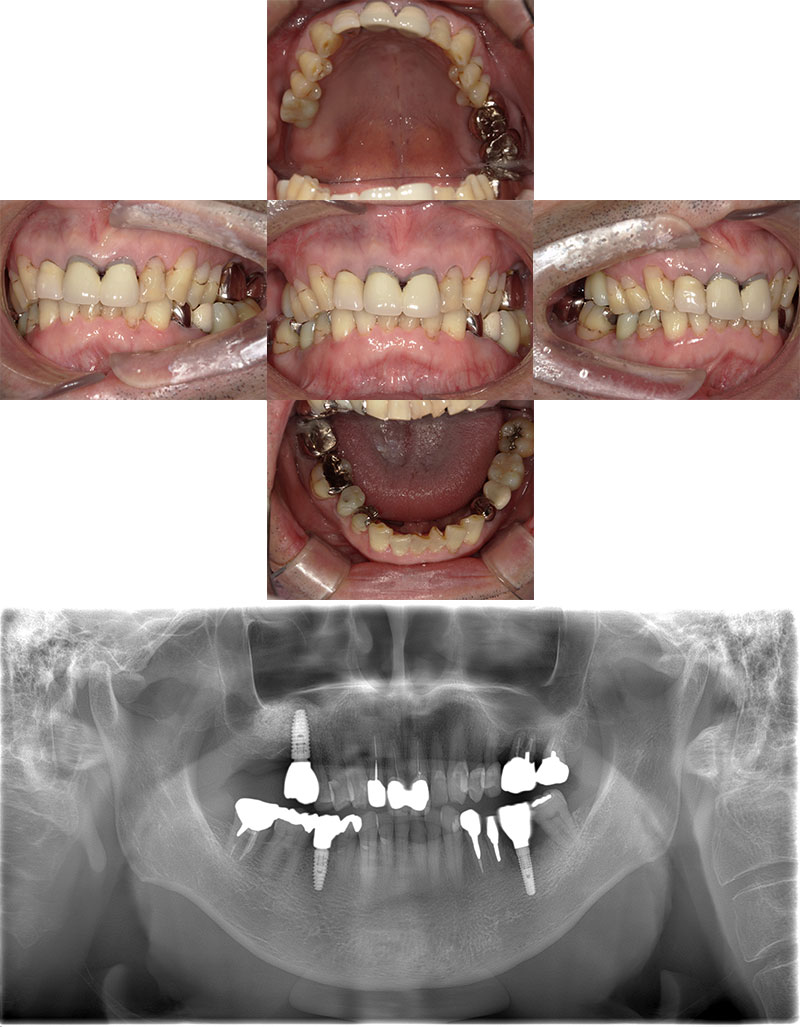

ワイヤー矯正+インプラント症例

治療前

Before

治療後

After

年齢 43歳

性別 女性

主訴 左下の乳歯を抜きたい